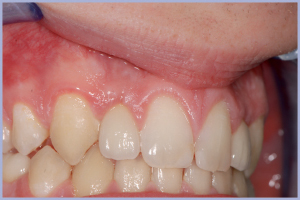

- Fig. 28 – Si può apprezzare il perfetto stato dei tessuti periimplantari

- Figg. 29, 30, 31 – Corona definitiva in zirconia ceramica, ben integrata a livello estetico e funzionale

- Fig. 30

- Fig. 31